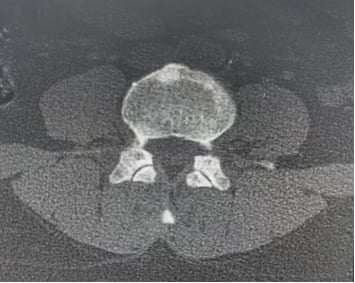

患者接受了规范的初始治疗:手术(左乳单切+SLNB+ALND),辅助化疗(AC-T*8周期),辅助放疗(患侧胸壁+锁骨上下区,50Gy/2Gy/25次),以及内分泌治疗(OFS+来曲唑)。2023年3月,为了强化治疗效果,医生为她加用了阿贝西利进行强化内分泌治疗。然而,尽管进行了积极治疗,疾病的进展依然迅速。2025年1月复查时疾病稳定,但仅两个月后,2025年3月强化内分泌治疗结束后,2025年4月复查就提示肺转移可能。胸部CT、骨扫描、头颅+腰椎CT等影像学检查均显示多发可疑病灶。最终,2025年5月的复查确诊为左乳癌术后肺、肝、左侧胸膜、骨转移,肝脏穿刺病理进一步证实为转移性腺癌,ER表达降至13%中+,PR阴性,HER2(2+),FISH阴性,再次确认HER2低表达。